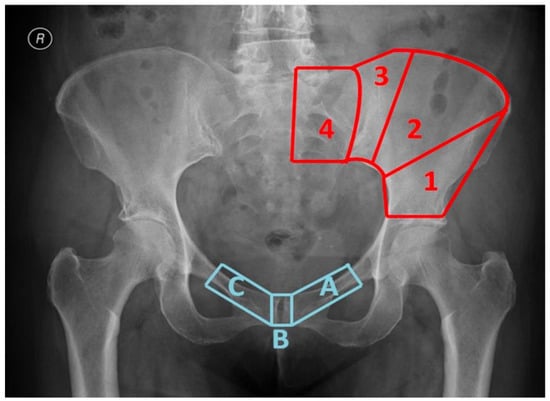

| Region of Proximal Osteotomy Line: | Region of Distal Osteotomy Line: |

|---|---|

| 1Osteotomy inside an area comprised between the roof of the acetabulum and a line that connects the apex of the ischiatic notch and the anterosuperior iliac spine | AOsteotomy involving the ipsilateral pubic ramus |

| 2Osteotomy inside an area comprised between the anterosuperior iliac spine and the lateral margin of posterosuperior iliac spine bone bulk | BOsteotomy involving the pubic symphysis |

| 3Osteotomy inside an area comprised between the lateral margin of posterosuperior iliac spine bone bulk and the sacro-iliac joint (excluded) | COsteotomy involving the contralateral pubic ramus |

| 4Osteotomy medial to the sacro-iliac joint (included) |